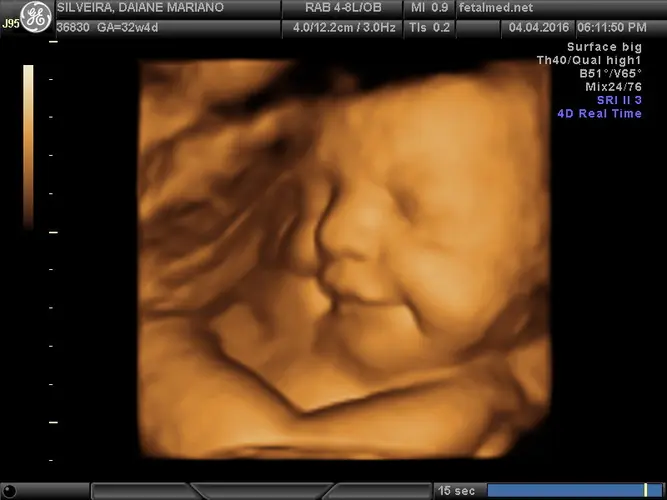

Dependendo do seu caso específico, pode ser solicitado um ultrassom para avaliar o crescimento fetal e a quantidade de líquido amniótico. Em algumas situações, exames como a dopplerfluxometria podem ser indicados para verificar o fluxo sanguíneo na placenta e no cordão umbilical.